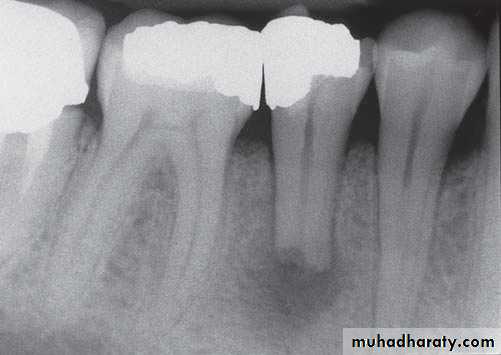

Acute pulpitis. Low-power view showing occlusal caries penetratingto the pulp through a layer of reactionary dentine. There is acuteinfl ammation localised to the pulp horn.

Acute pulpitis. Beneath the carious exposure (top right) a denseinfl ammatory infi ltrate is accumulating. More deeply, the pulp is intenselyhyperaemic.